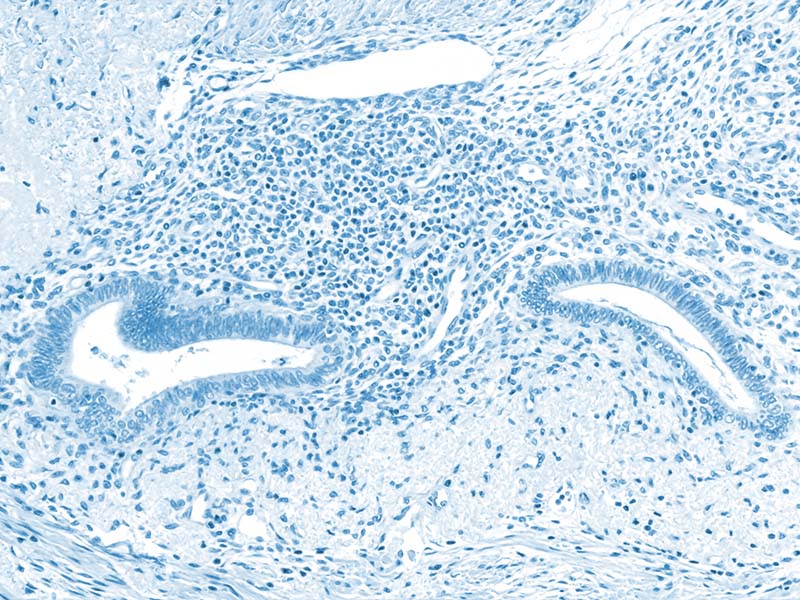

Endometriosis occurs when tissue similar to the lining of the uterus grows outside the uterus, on ovaries, fallopian tubes, the pelvic lining, or other organs. These growths respond to menstrual cycles, causing inflammation, pain, and scarring.

• Endometrial hyperplasia is when cells in the uterine lining grow too much, causing abnormal thickening. Usually, this is not a sign of cancer.

• Endometrial atypical hyperplasia (EAH) – when the cells themselves look abnormal under a microscope – can progress to endometrial cancer in 20% to 50% of cases, depending on various risk factors.

Atypical Endometriosis

In rare cases, doctors have found a form of endometriosis where the cells look unusual (“atypical”), which might represent a middle step between endometriosis and cancer. But this doesn’t happen often, and most cases of endometriosis never turn into cancer.